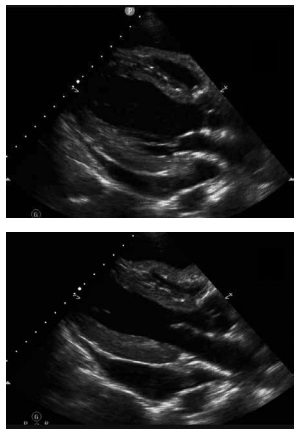

Um paciente de 41 anos de idade, hipertenso,

em uso de losartana, com queixa de dispneia durante os

esforços e desconforto precordial inespecífico nas últimas

semanas. Seguem imagens do ecocardiograma a seguir.

Com base nessa situação hipotética e nas imagens acima, assinale a alternativa que apresenta a etiologia adequada do quadro.